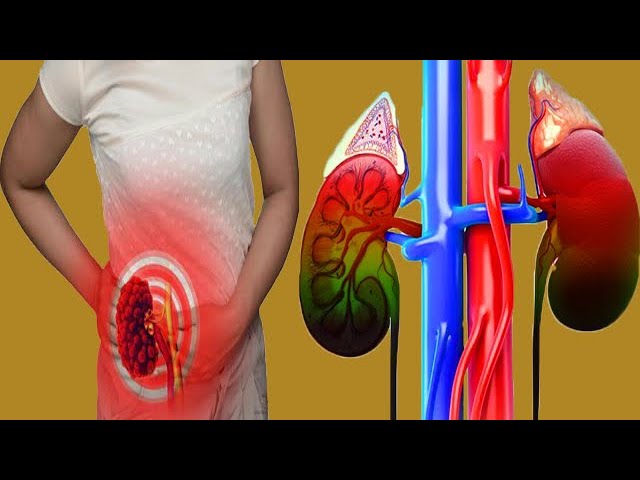

Natural treatments for kidney stones, infections, and other kidney-related issues.